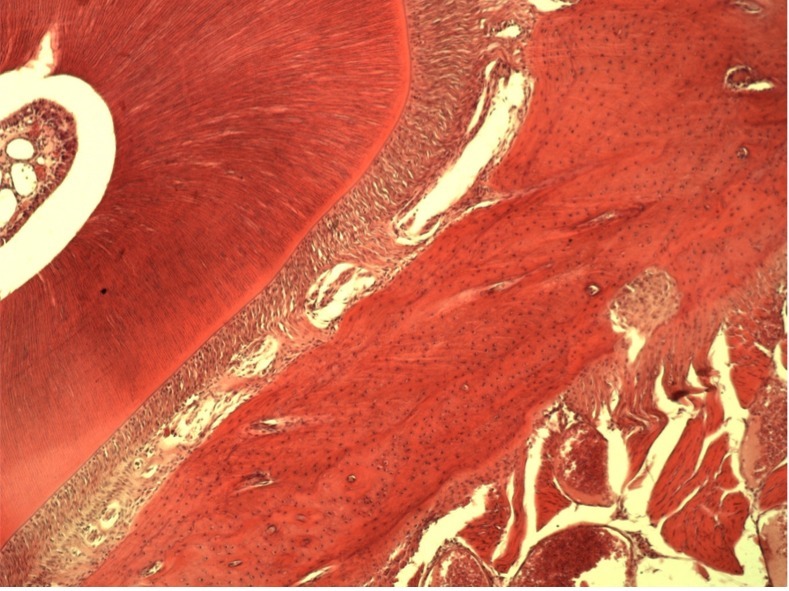

• Все материалы и препараты для стоматологии полностью резорбируются и замещаются собственными тканями на 100%.

• Например, таким образом удаляются все следы жира, белка, нуклеиновых кислот, мертвых клеток и их компонентов, неколлагеновых белков и прочих соединений. Вследствие такой очистки остается только коллагено-минеральный каркас мертвого межклеточного вещества костной ткани, состав которого стабилен на протяжении всей жизни человека.

• Минерализованную губчатую или кортикальную кость применяют там, где нужно сохранить объем по высоте и ширине, например, при операции поднятия верхнечелюстного синуса или операции имплантации зубов.

• Деминерализованную кость применяют дополнительно для восстановления внутренних костных дефектов: через нее лучше растут кровеносные сосуды, так как она содержит морфогенетический белок (МГБ), но за счет отсутствия минерального каркаса не способна удержать трехмерный объем.